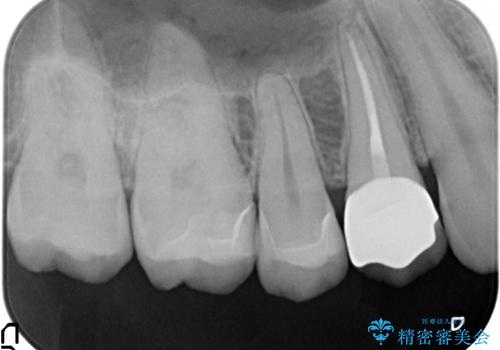

銀歯・虫歯を丁寧に除去し、残存歯質にピッタリと合ったセラミック修復を計画します。

- 25万円(emaxインレー×2・仮歯・ファイバーコア・ジルコニアクラウン)費用は治療当時の料金となります

修復物は歯にピッタリと精密な形で形成。印象をする必要があります。

拡大鏡を用いた精密な形成や、シリコン印象を行うことで精度の高い修復処置を行うことができます。